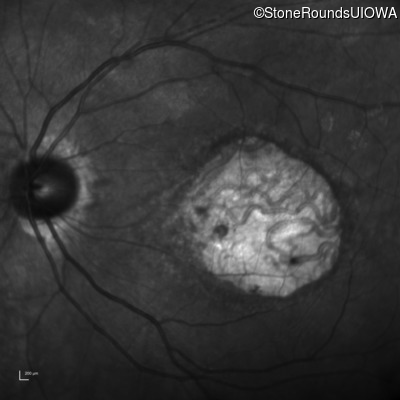

Infrared Fundus Photograph - Right - 20/50 -1

Exemplar